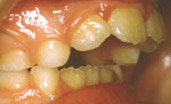

Как правило, первые вредные привычки, способные привести к нарушениям прикуса, формируются у ребёнка ещё до 1,5 лет. Наиболее распространенная из них - сосание большого пальца, языка или пустышки. Если сосательный рефлекс не угасает после года, это свидетельствует о задержке созревания тех или иных функциональных систем в организме. К трехлетнему возрасту у детей, постоянно сосущих палец или соску формируется открытый прикус.

Привычка ребенка сосать большой палец приводит к сужению верхней челюсти и асимметричной деформации ее во фронтальном отделе. При этом язык, располагаясь на нижних зубах, не поддерживает свод верхней челюсти, и поэтому баланс воздействующих на неё мышечных сил нарушается. Дополнительное давление щечных мышц усугубляет сужение зубных рядов в боковых отделах, следствием чего становится латеральный перекрестный прикус. Помимо того, давление, оказываемое большим пальцем на нижний зубной ряд, вызывает лингвальное смещение резцов и усугубляет недоразвитие нижней челюсти. У детей постарше, начиная с 3-х лет, довольно часто встречается привычка прикусывать нижнюю губу, что приводит к уплощению фронтального отдела нижнего зубного ряда.